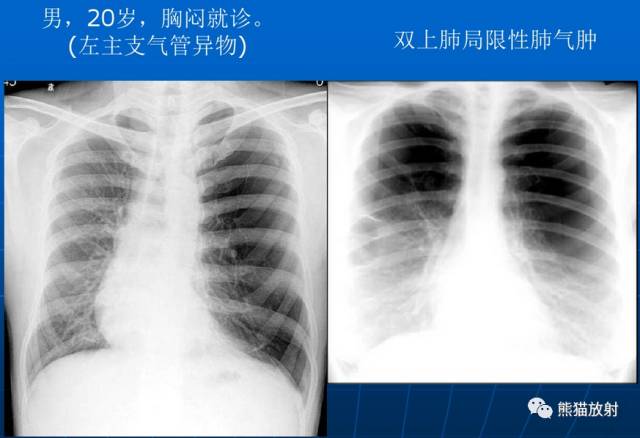

局限性阻塞性肺气肿是由于一个较大的支气管产生部分性阻塞所引起。该病可见于支气管内异物、小儿急性肺炎、早期支气管肿瘤和支气管慢性炎性狭窄包括结核等病史。

X线表现:在肺野内有局部的透亮度增高区域,其部位和范围取决于支气管部分阻塞的所在。至于有无胸廓、横膈等改变取决于病变的范围和部位。

| 局限性阻塞性肺气肿 |